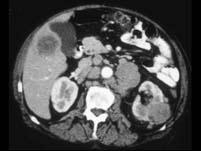

问题 男,54岁,左侧腰痛,伴间歇性血尿2个月余,请结合图像,下列哪项描述正确 ( )

选项 A、左肾转移癌 B、腹主动脉旁及左肾门区淋巴结转移 C、肝内多发转移癌 D、肝癌 E、左侧肾癌

答案 BCE